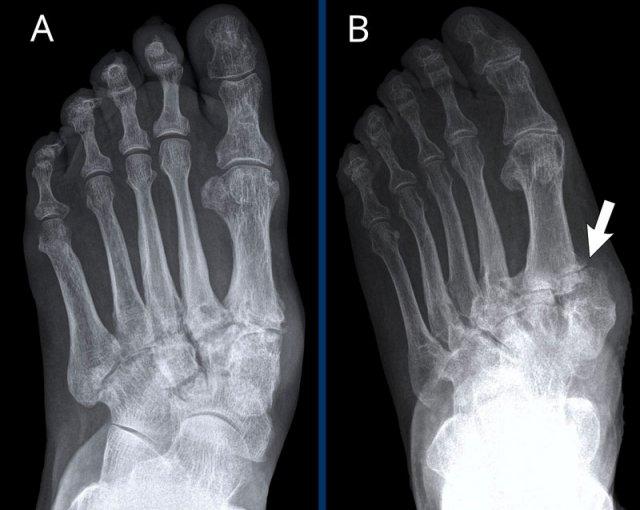

Biến dạng bút chì trong cốc

A. Biến dạng bút chì trong cốc tại ngón chân thứ 1 và thứ 5.

B. Tiêu xương đầu ngón (acro-osteolysis) với tiêu xương chỏm đốt ngón xa của ngón 2-4 và 5.

Có bào mòn xương tại khớp bàn ngón chân (MTP) 2 và 3.